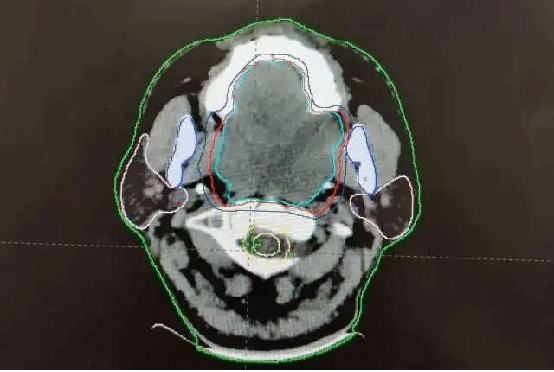

渴望收获安稳睡眠的路先生辗转来到我院放疗科就诊。科室团队迅速启动多学科会诊,针对肿瘤体积大、位置特殊、紧邻重要器官的复杂情况,制定了个体化精准放疗方案。借助先进的影像及放疗技术,团队精准勾勒肿瘤靶区,将高剂量射线精准聚焦于病灶,在最大限度保护周围正常组织的同时,对肿瘤展开集中“攻坚”。

治疗前